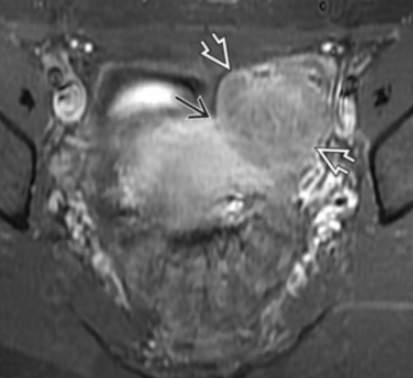

Peritoneal Inclusion Cyst

• Basically cyst in the pelvis

• Very commonly arises next to/surrounds the ovary

• Seen in women of reproductive age

• May have septation

• Not your typically well circumscribed cyst, its basically if there is inflammation and scarring or whatever and it walls off a fluid collection that is sterile (not an abscess)

• Looks like a non circular cyst around ovary usually